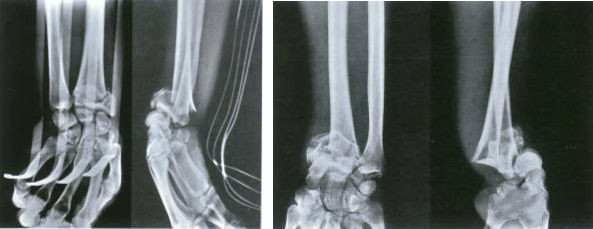

Перелом лодыжки внутрисуставной.

Целью лечения является восстановление нормального анатомического строения суставов.

Сроки операции зависят от состояния мягких тканей.

Идеальное время для операции – до появления отека и волдырей в области перелома.

Это опора для людей, чтобы стоять и ходить.Восстановление нормальной анатомической структуры стопы играет жизненно важную роль в процессе стояния и ходьбы.

Как и при переломах лодыжки, сроки операции зависят от степени и состояния отека мягких тканей.